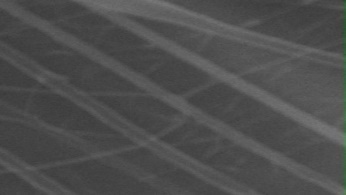

Morphology, size and size distribution of the nanofibres

Morphology analysis was adapted from Aytac et al. (2019) [38]. The SEM analysis was conducted to detect electrospun nanofibers' fibre shape and diameter. The electrospun nanofibres from 18 runs were investigated individually by SEM (FEI, quanta 450, Czech). Images revealed the morphology of resultant nanofibers and measured their diameters in nanometres. The average number of records was calculated using a standard deviation estimation. The setting of the SEM machine was conducted on voltage 25.00 kv, magnification 23624 and width (8.3-9.3 mm).

Results of the SEM analysis are listed in table 2, with a wide range of fibre diameters starting from 87.2 nm (run 13) to 2500 nm (run 18). Run 18 did not produce true nanofibers due to the deficient concentration of PVA. The statistical analysis revealed that the effect of each polymer (factor) on the diameter size of the electrospun nanofiber was vast. Therefore, there is a correlation between factors A, B and C and fibre diameter as expressed in equation 5.

Fig. 3: Nanofibres SEM images with nanofiber diameter frequencies. The PVA, PEO and HPMC were symbolised as V, E and P. Data are given in mean±SD, n=3

The morphology of nanofibers would be affected by device parameters such as flow rate, voltage and distance from the collector. Also, nanofibres' properties could be changed due to temperature and humidity. The bead formation appears with a low concentration of PVA (run 2) or a high concentration of PEO and HPMC (runs 6 and 11), as shown in fig. 3. Therefore, increasing PVA concentration leads to beads' disappearance and smooth fibres' formation. Nageeb El-Helaly (2021) and Silva J. A. et al. (2021) reported similar results [47, 48]. Kalluriet al.(2021)[49] studied the relationship between the fibre diameter, bead diameter and flow rate. Thus, they concluded that better fibre uniformity and bead formation were needed at a high flow rate. These results appear clearly in run two and run six and agree with Silva et al.(2021) results [50], who reported that only the concentration of PVA (≥ 15%) could produce uniform nanofibers when using the lower molecular weight of PVA (67,000). Fibre diameter of 15% PVA and more appeared to be in the range 87.11 to 252.5 nm with uniform fibres and disappearance of beads except in run 6, where the beads appear due to increasing the concentration of HPMC as highlighted by Gripet al. (2018) [46].